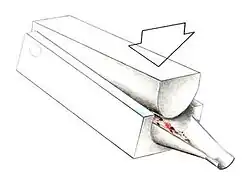

In attempts to address the weaker structure of the reparative fibrocartilage, new techniques have been designed to fill the defect with tissue that more closely simulates normal hyaline articular cartilage. One such technique is autologous chondrocyte implantation (ACI), which is useful for large, isolated femoral defects in younger people. In this surgery, chondrocytes are arthroscopically extracted from the intercondylar notch of the articular surface. The chondrocytes are grown and injected into the defect under a periosteal patch. ACI surgery has reported good to excellent results for reduced swelling, pain and locking in clinical follow-up examinations.[58][59] Some physicians preferred to use undifferentiated pluripotential cells, such as periosteal cells and bone marrow stem cells, as opposed to chondrocytes. These too have demonstrated the ability to regenerate both the cartilage and the underlying subchondral bone.[60]

Similar to OATS, arthroscopic articular cartilage paste grafting is a surgical procedure offering cost-effective, long-lasting results for stage IV lesions. A bone and cartilage paste derived from crushed plugs of the non-weight-bearing intercondylar notch can achieve pain relief, repair damaged tissue, and restore function.[61]